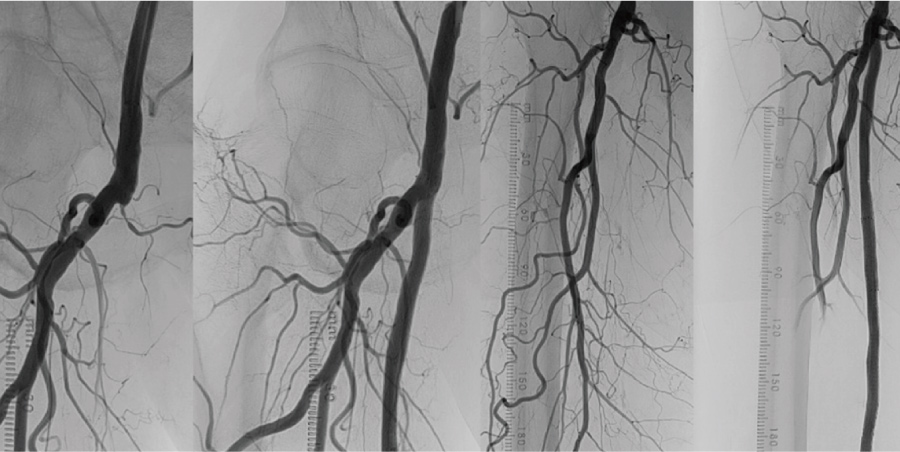

02急性下肢閉塞_before

別疾患で入院中だった患者様が急性下肢閉塞を起こしましたが、 速やかな治療で改善し、2 日後に退院しました。

02急性下肢閉塞_after

03

腹部大動脈から両下肢腸骨動脈の血管内を治療しました。治療翌日に自ら歩いて帰られました。